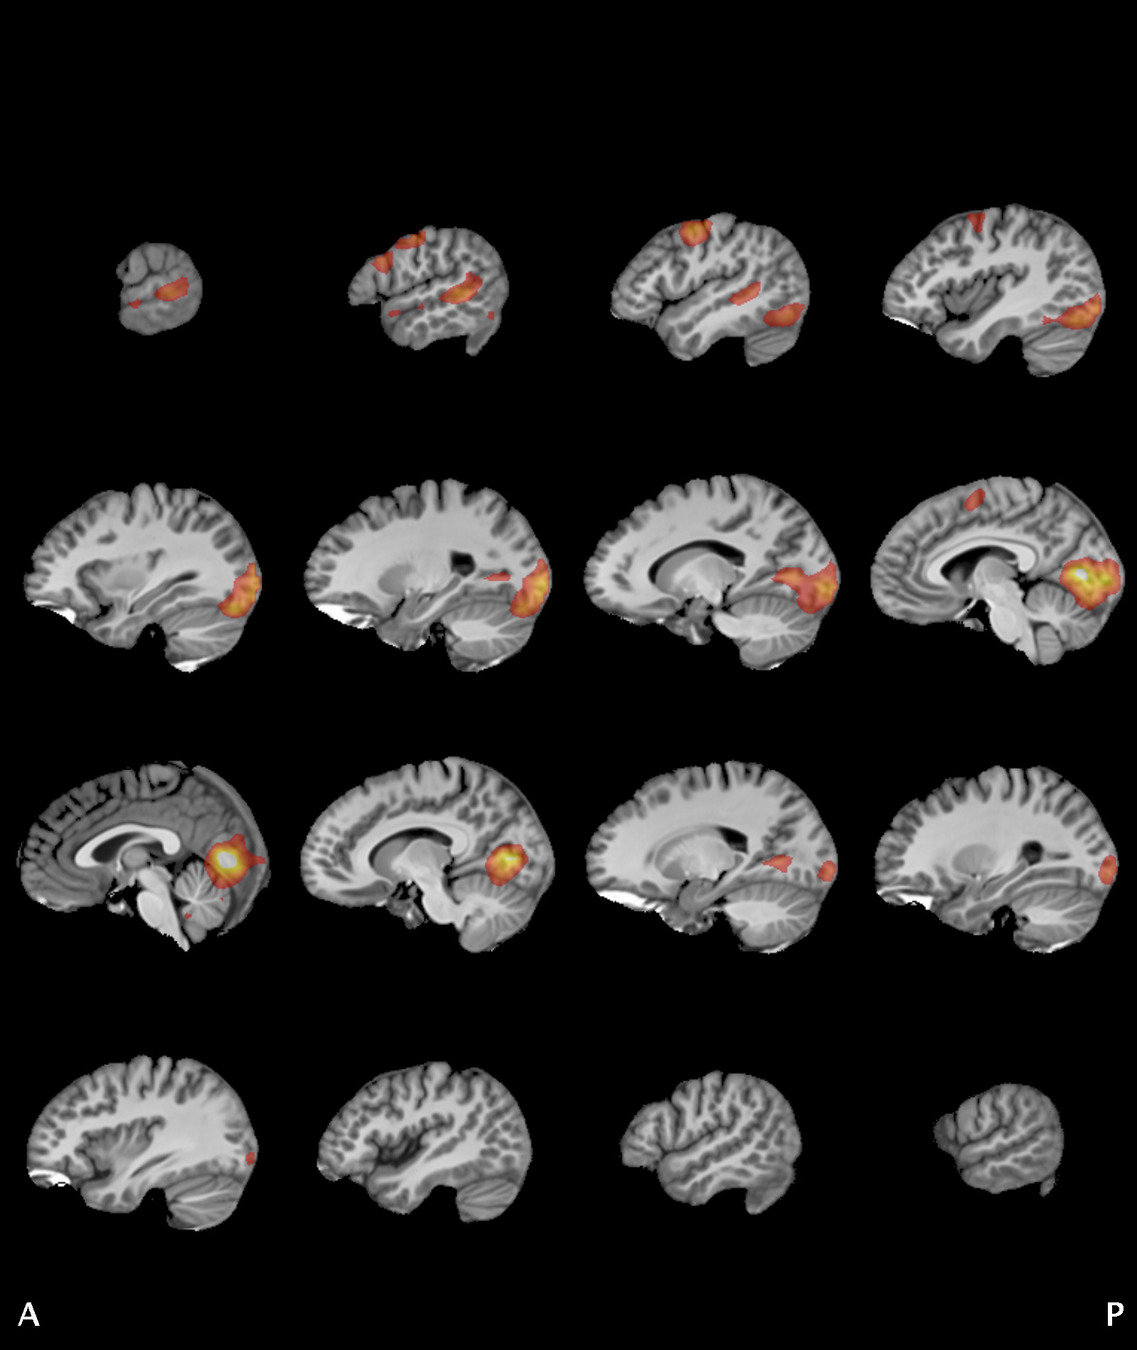

Results

Significant ROIs

Voxels Peak - x Peak - y Peak - z Anatomical location

1923 -1.5 79.5 -9 R/L Lingual Gyrus

495 52.5 -10.5 -18.0 L. Mid. Temporal Gyrus

395 46.5 16.5 33.0 L. Precentral Gyrus

135 1.5 38.5 -12.0 L. Ant. Cerebellum

56 7.5 19.5 -3.0 L. Thalamus

55 -22.5 -94.5 -9.0 R. Inf. Occipital Gyrus

55 52.5 -7.5 15.0 L. Inf. Frontal Gyrus

54 4.5 7.5 60.0 L. Medial Frontal Gyrus

29 -46.5 -7.5 -24.0 R. Temporal Pole